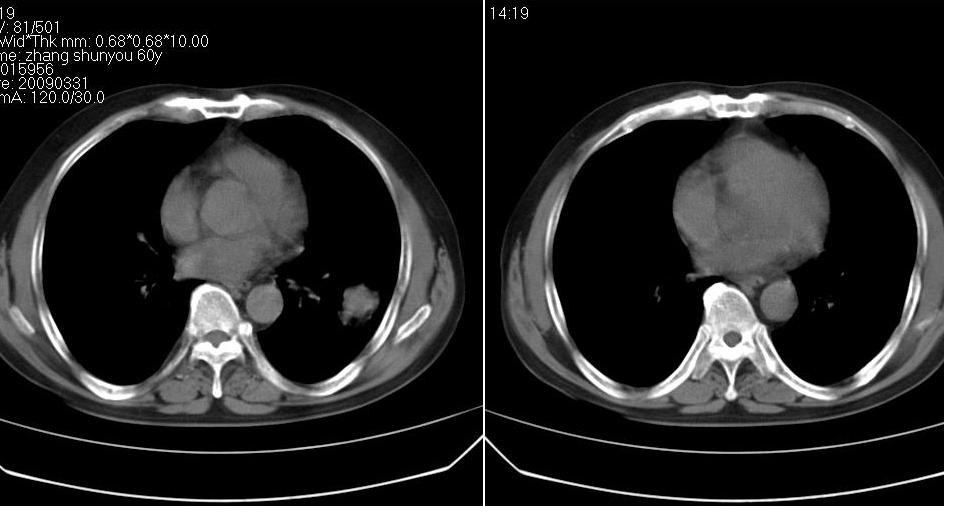

男 60岁,咳嗽,喀痰,胸闷,有吸烟史,正常图片未上传,请谅解。

左肺肿块有分叶、有毛刺,符合周围型肺癌。

分叶状肿块,有毛刺,有晕,有粗纹理直通肺门,支持考虑周围型肺癌

考虑肺癌建议强化